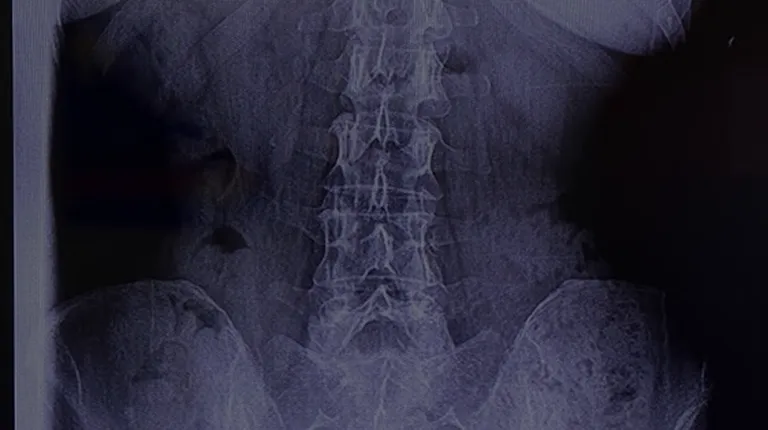

Cervical spine

Wow, I can't say enough about how well treated I have been at Shipley. I had been hesitant to come to a chiropractor due to my medical and physical conditions, yet Jordan reassured me every step of the way. He made sure to let me know that I get to decide how little or how far we go. The best part is I felt extremely validated about the pain I was feeling through X-rays, improvement and just common courtesy of education from staff. Lastly, the doctors were extremely flexible for appointments and hours, which is so helpful, especially if you randomly get twisted up or have debilitating tension. I would call before they even open to the doctors answering the phones and fitting me in ASAP. My only minor complaint is that the office space is pretty old school and could use a remodel - but do not let that deter you from coming here! I will be continuing to come here for the duration of time I need care and in the future.